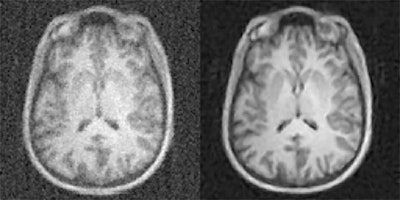

The method, called automated transform by manifold approximation (AUTOMAP), uses a deep neural network to automatically determine the correct image reconstruction algorithm. Producing higher-quality images from less data, the model delivers quantifiable improvements in image quality and noise reduction, according to the team led by Bo Zhu, PhD, a research fellow at MGH's Athinoula A. Martinos Center for Biomedical Imaging.

AUTOMAP provides a new paradigm for image reconstruction that learns a reconstruction function for arbitrary acquisition strategies in order to reduce artifacts and improve reconstruction accuracy for noisy and undersampled image acquisitions, according to the researchers.